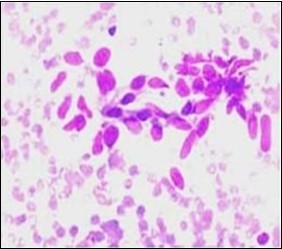

On microscopy, a collagen- rich, minimally cellular, fibrotic soft tissue nodule is exemplified which simulates a scar or conventional fibroma. The neoplasm is comprised of uniform, plump, fibroblastic or myo-fibroblastic cells encompassed in a collagen-rich stroma with infiltration and entrapment of skeletal myocytes 5, 6. Cogent histological examination depicts replacement of muscle fibres and muscle mass with fascicles of fibrous tissue comprised of mature fibroblastic cells, thereby conferring fibrosis 6. Figure 1, Figure 2, Figure 3, Figure 4, Figure 5, Figure 6, Figure 7, Figure 8.

Figure 4.Fine needle aspiration cytology of fibromatosis colli delineating aggregates of plump, spindle-shaped cells admixed with fibroblasts, fibro-connective tissue fragments and intermingled red cell extravasation 11

Figure 5.Fine needle aspiration cytology of fibromatosis colli exhibiting aggregates of spindle- shaped cells, plump fibroblasts, fibro-connective tissue fragments and a clear background with minimal red cell extravasation 12.